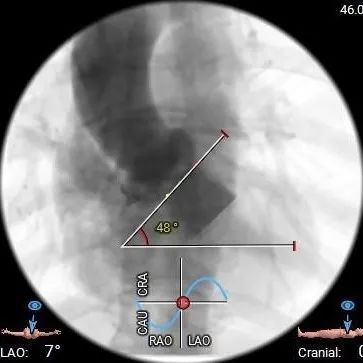

术前CT评估

三叶式主动脉瓣,瓣叶显著增厚伴轻度钙化,LVOT偏直筒;水平夹角约48°

• 主动脉瓣水平夹角约48°,非横位心,主动脉弓宽度角度可;